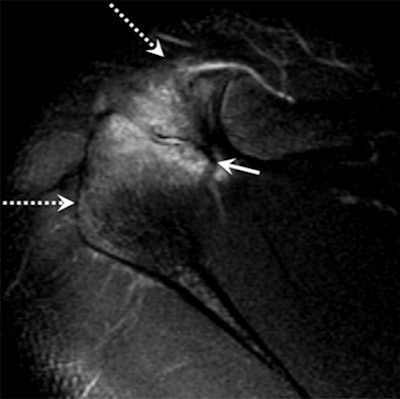

Image above shows incomplete fusion with moderate bone marrow edema in an 18-year-old male pitcher with acromial apophysiolysis. MR image below in the same patient at age 25 after quitting pitching shows complete fusion and resolution of the previously seen acromial edema (dashed arrows). Images courtesy of Radiology.

The researchers found that 25 (86%) of the 29 acromial apophysiolysis patients with follow-up imaging showed os acromiale, or incomplete fusion, compared with just one person (4%) out of 23 in the control group. Meanwhile, 15 (68%) of 22 acromial apophysiolysis patients had rotator cuff tears, compared with six (29%) of 21 control subjects.

"They never fused that bone at the acromion, so they developed what is called os acromiale," Roedl told AuntMinnie.com. "The majority of patients who stopped pitching after the diagnosis had no long-term adverse effects."